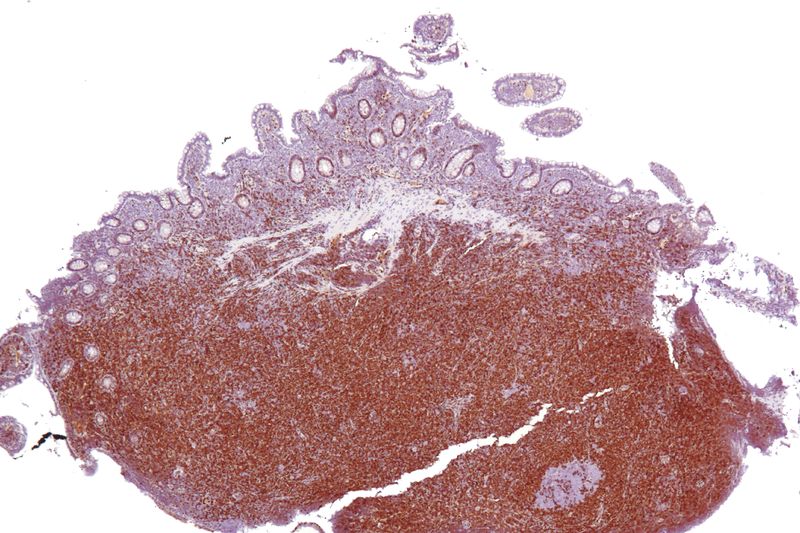

Mucosa associated lymphoid tissue (MALT) lymphoma is a mucosal-site marginal zone lymphoma.

Treatment for H Pylori may cause the gastric MALT lymphoma to regress.